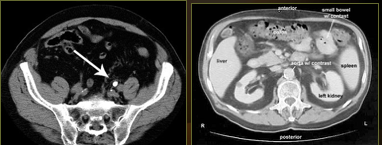

What type of diagnostic test is shown here?

CT abdomen with contrast

What is this image showing?

Pancreatitis

Left image: upper abdominal CT scan shows inflammation and swelling of the pancreas. Consistent with acute pancreatitis.

Right image: CT scan of the upper abdomen showing multiple white-colored calcifications. These occur in chronic pancreatitis.